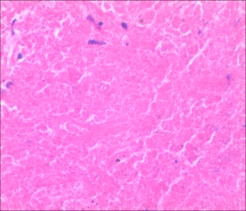

2.抗酸染色在结核病病理学诊断具有重要作用

一般情况病理石蜡组织切片,结核结节的坏死区中心或坏死区与上皮样肉芽肿交界处较容易查见抗酸菌,抗酸菌阳性对结核病诊断有重要的提示作用。